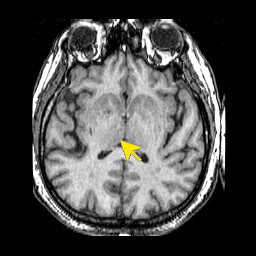

075diencephalethalamus.png